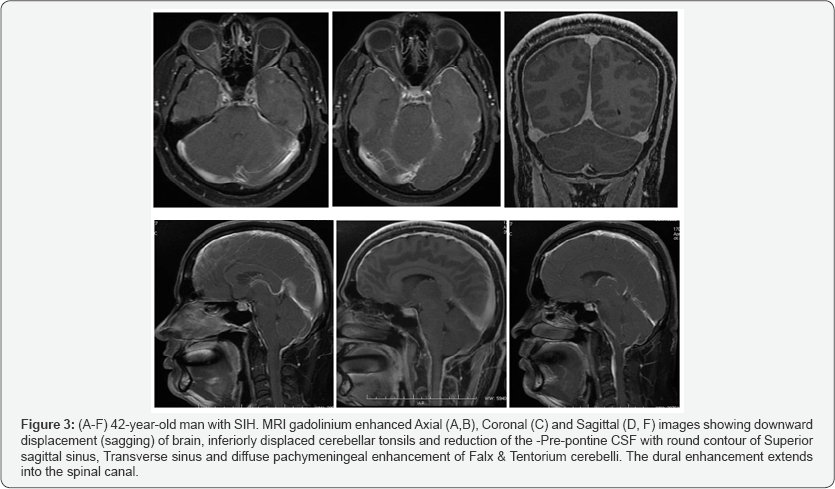

After contrast media injection, there was diffuse and uniform intense enhancement of all the dural surfaces, including the Falx and tentorium. The thickened and enhancing dura showed a smooth, non-nodular pattern (Figure 2A-2F). In addition, there was venous engorgement of the superior sagittal and transverse sinuses and prominent hyperaemic enhancement of the pituitary gland. The brain was sagging, with inferiorly displaced cerebellar tonsils and decreased pre-pontine CSF space (Figure 3A-3F).

Sagging and downward displacement of the cerebellar tonsils or effacement of prepontine cistern with flattening of the pons against the clivus [7] may mimic a Chiari type1 malformation or it can be misdiagnosed as increased intracranial pressure from space-occupying lesions. Downward drooping of splenium of the corpus callosum (droopy penis sign) and decreased fluid within the optic nerve sheath are the other signs. These qualitative features are not always present, so quantitative findings would be of great help in making more accurate diagnosis based on MRI findings.

Venous engorgement is defined as prominent dural venous sinus enhancement with enlarged and rounded sinuses [4]. On sagittal T1-weighted MRI, the convex bulging of the inferior border of the dominant transverse sinus seen in intracranial hypotension patients has been described as the “venous distention” sign [29]. Brainstem slumping is defined as a low- lying third ventricle at or below the level of the floor of the sella turcica, horizontal configuration of the infundibulum, and red nuclei below the level of the tentorium [30].

Several imaging features of brainstem slumping have been identified and described in the literature including ventricular effacement [7], effacement of the suprasellar and prepontine cisterns, bowing of the optic chiasm over the sella turcica, flattening of the central pons [30], and caudal displacement of the cerebellar tonsils [1,4,11].